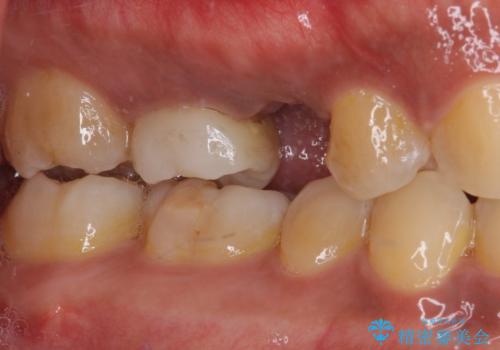

- 上下前歯部の叢生を気にして来院された患者様です。

レントゲン撮影により、右上奥歯が折れていることが分かりました。

患者様自身も何となく違和感を覚えていたとのことで、インプラント補綴治療を行うこととしました。

歯列不正は比較的軽微であったので、インビザラインによる矯正治療とし、矯正治療中にタイミングを見て抜歯とインプラント埋入を行う予定としました。